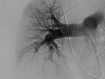

This is a case of a woman with massive hemoptysis, associated with a pulmonary artery pseudoaneurysm, and a fistula between the right pulmonary artery and bronchus intermedius. Bronchoscopic evaluation revealed an endobronchial mass in the right bronchus intermedius, suspicious for a tumor. Upon biopsy of the mass, massive bleeding occurred. The right lung was surgically resected. No specific etiology for the fistula was identified on pathologic examination. To our knowledge, this is the first report of a pulmonary artery-bronchial fistula presenting without typically known predisposing factors.